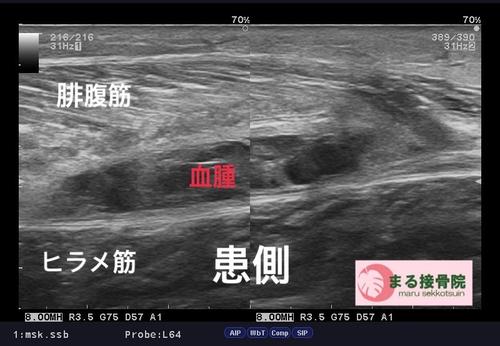

今日の患者様は、テニス中、ふくらはぎが「誰かに後ろから蹴られた、、、ような」「力を入れた時にブチッ!!と痛みがはしった、、、」と御来院。

肉離れはスポーツ中、日常生活で階段を駆け上がるなど、筋肉に急激な力が加わった時に、筋繊維が損傷した状態。

治療は、しっかり問診、触診、視診を行い、超音波画像診断装置で患部状態、深さ、広さをしっかり確認し、早期復帰、回復に向けて対処していきます。

まずは患部の出血、腫れを最小限に抑え、周囲の筋肉も硬くならないようにし、タイミングを診てストレッチ、リハビリを行って参ります。